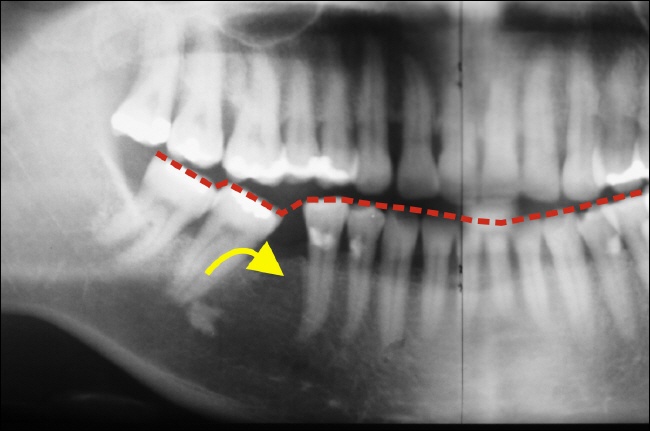

Fehlt nun ein Zahn, so ist eine typische Folge die, dass die Zähne in die vorhandene Lücke kippen.